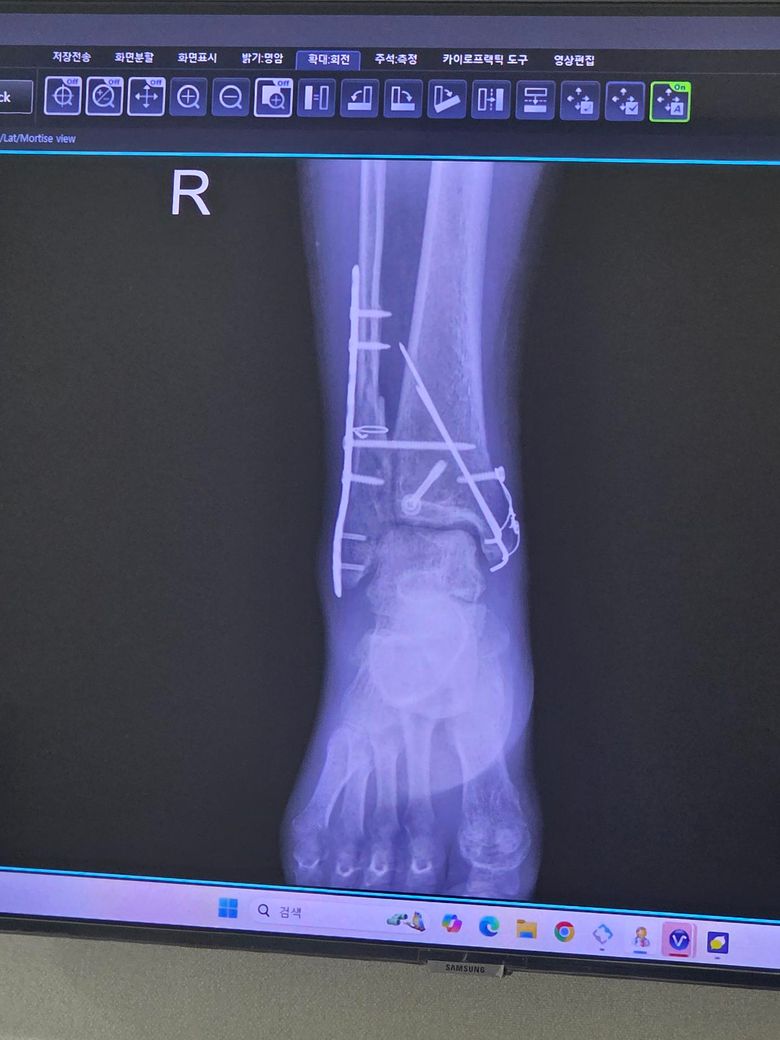

발목 삼과골절 12주차 질문입니다.

발목 삼과골절 수술후 12주차 입니다만 발 디딜때 통증으로 아직 보조기와 목발 2개(아주 가끔 1개 사용)사용중 입니다.

• 1번 째 사진